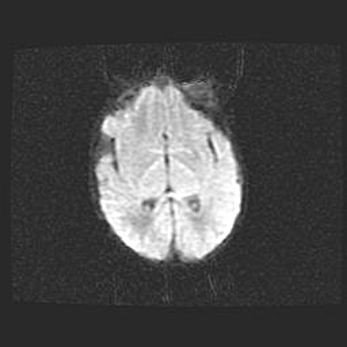

Сообщающаяся гидроцефалия. Кистозная энцефаломаляция головного мозга.

Возраст: 3 месяца 4 дня

Вес: 3100 г

Пол: женский

Окружность головы: 34 см

Срок гестации: 31 неделя

Кистозная энцефаломаляция головного мозга - одна из форм поражения головного мозга в детском возрасте. Характеризуется возникновением множественных и распространённых кист в коре, белом веществе и подкорковых образованиях головного мозга у плодов, новорождённых и детей раннего возраста. Развитие кистозной энцефаломаляции связано с внутриутробной асфиксией и гипотонией, родовой травмой, тромбозом синусов, пороками развития сосудов, инфекциями, сепсисом и другими причинами. Наиболее значимые инфекционные агенты: вирусы простого герпеса, цитомегалии, краснухи, токсоплазмы, энтеробактерии, золотистый стафилококк и другие.